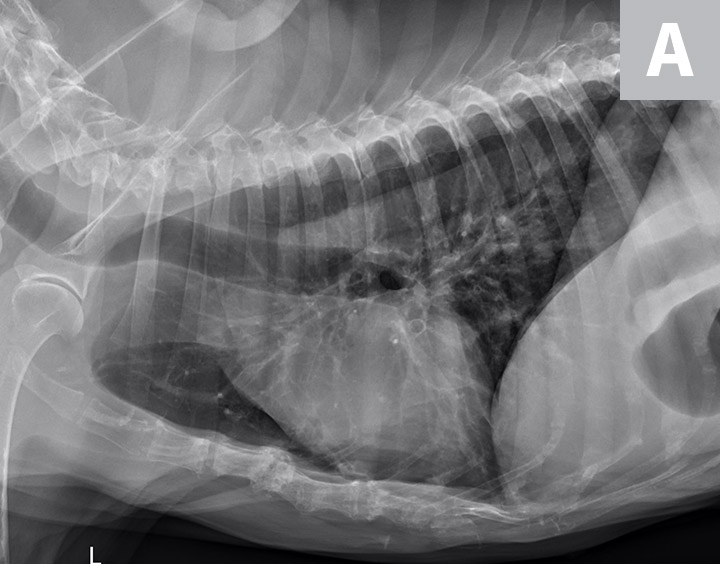

From todaysveterinarypractice.com

Canine Chronic Bronchitis A Review and Update Today's Veterinary Can Dog Hair Cause Bronchitis learning how to recognize the signs of dog bronchitis can help you identify the cause and help your coughing dog feel better soon. when inhaled, dog hair can cause allergic reactions, such as sneezing, coughing, and runny nose, or trigger more severe symptoms, such. learn more about the relationship between pet dander and bronchitis, and whether your. Can Dog Hair Cause Bronchitis.